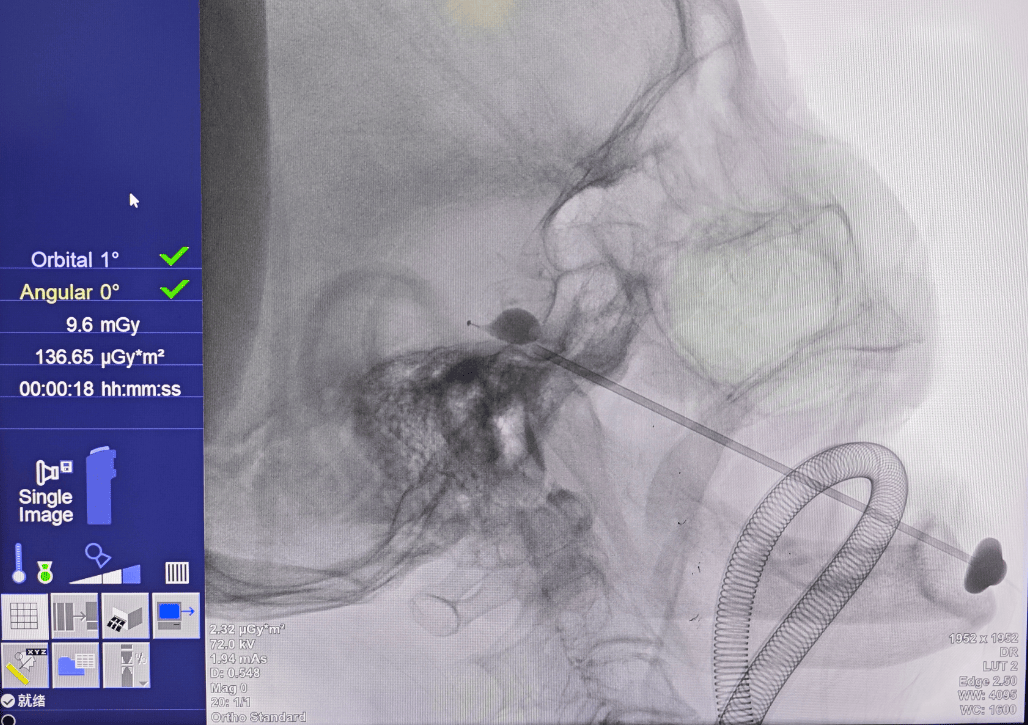

10月16日,手术如期进行。在景主任和赵主任的默契配合下,麻醉、消毒、穿刺等步骤有序推进。然而,就在要把球囊放进指定位置时,陈奶奶突然心跳变慢,情况危急。

赵主任马上撤出球囊,麻醉医生迅速处理,仅10秒钟,陈奶奶缓了过来。随后,两位主任再次小心操作,成功完成手术,陈奶奶平安返回病房。